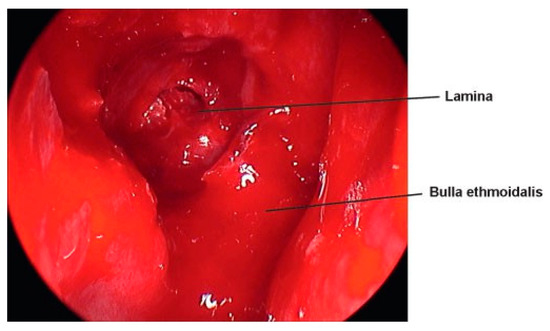

Medial orbital fractures are treated similarly to floor fractures except that these require more extensive knowledge of intranasal anatomy. To undertake the endoscopic repair, you must be aware of endoscopic skull base anatomy and be comfortable taking or medializing the middle turbinate and taking the uncinate process and ethmoid bulla down (Figure 8). If you can do this, you can have a full view of the lamina papyracea (Figure 9). Once the lamina is identified, you can ballot and find the defect. This is then most easily repaired with a Silastic sheet of sufficient stiffness to prevent herniation of the orbital contents. A thin Medpor sheet may also be used (Figure 10).

Figure 9. Uncinate to the left upfront, bulla taken down, and the anterior ethmoid exposed.